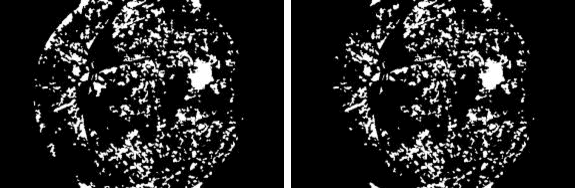

Abstract:This research aims to develop an efficient system for screening of diabetic retinopathy. Diabetic retinopathy is the major cause of blindness. Severity of diabetic retinopathy is recognized by some features, such as blood vessel area, exudates, haemorrhages and microaneurysms. To grade the disease the screening system must efficiently detect these features. In this paper we are proposing a simple and fast method for detection of diabetic retinopathy. We do pre-processing of grey-scale image and find all labelled connected components (blobs) in an image regardless of whether it is haemorrhages, exudates, vessels, optic disc or anything else. Then we apply some constraints such as compactness, area of blob, intensity and contrast for screening of candidate connectedcomponent responsible for diabetic retinopathy. We obtain our final results by doing some post processing. The results are compared with ground truths. Performance is measured by finding the recall (sensitivity). We took 10 images of dimension 500 * 752. The mean recall is 90.03%.